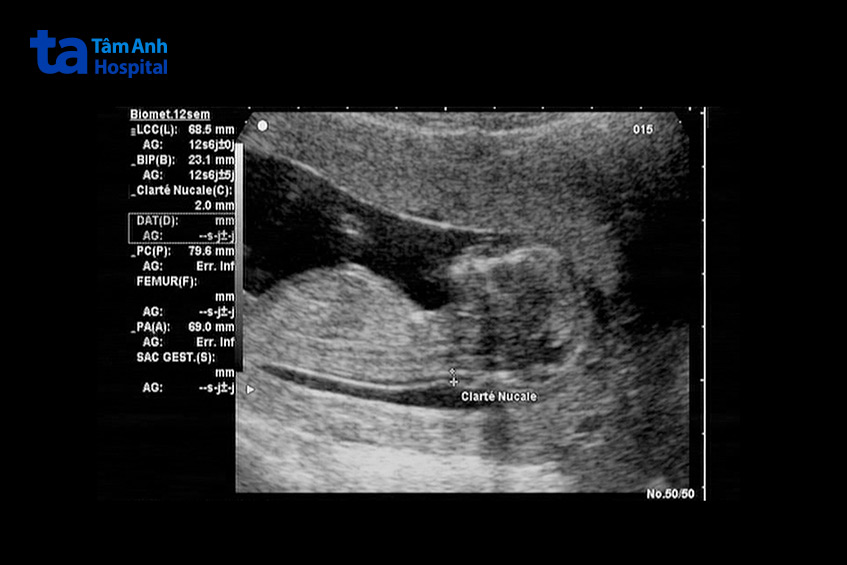

Trên siêu âm, thai IVF 12 tuần có hình dạng và kích thước như sau:

Hình ảnh siêu âm cung cấp thông tin chi tiết về sự phát triển của thai IVF 12 tuần, giúp bác sĩ theo dõi sát sao tình trạng của mẹ và bé.